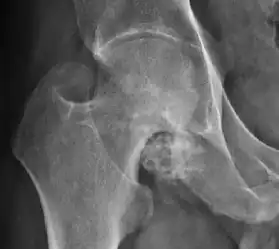

Plain radiography allows us to categorize the hip as normal or dysplastic or with impingement signs (pincer, cam, or a combination of both). Besides these, pathologic processes like osteoarthritis, inflammatory diseases, infection, or tumors can also be identified (Figure 1).[1]

Figure 1.

-

Radiography in normal hip -

X-ray in pincer impingement type of hip dysplasia -

X-ray of cam -

Hip in osteoarthritis -

Septic arthritis

In adults, one of the main indications for radiographs is the detection of osteoarthritic changes (Figure 1(e)). Nevertheless, radiographs usually detect advanced osteoarthritis that can be graded according to the Tönnis classifications. The grading system ranges from 0 to 3, where 0 shows no sign of osteoarthritis. Intermediate grade 1 shows mild sclerosis of the head and acetabulum, slight joint space narrowing, and marginal osteophyte lipping. Grade 2 presents with small cysts in the femoral head or acetabulum, moderate joint space narrowing, and moderate loss of sphericity of the femoral head. Grade 3 is the severest form of osteoarthritis, which manifests as severe narrowing of the joint space, large subchondral cyst with productive bone changes that may lead to deformity of the bone components of the joint, while secondary osteoarthritis due to calcium pyrophosphate deposition can be diagnosed when calcification of hyaline cartilage and fibrocartilage is detected.[1]

There are other pathological conditions that can affect the hip joint and radiographs help to make the appropriate diagnosis. Acute bacterial septic arthritis can be diagnosed by radiographs when a fast regional osteoporosis and destructive monoarticular process develops (Figure 1(f)). In case of tuberculous or brucella arthritis it is manifested as a slow progressive process, and diagnosis may be delayed.[1]

Synovial chondromatosis can be confidently diagnosed by X-ray when calcified cartilaginous chondromas are seen. However, other synovial proliferative processes, such as pigmented villonodular synovitis, require MRI for accurate diagnosis, although noncalcified synovitis can be suspected in radiographs by indirect signs, such as soft tissue swelling and/or erosions in the femoral head, femoral neck, or acetabulum (Figure 7).[1]